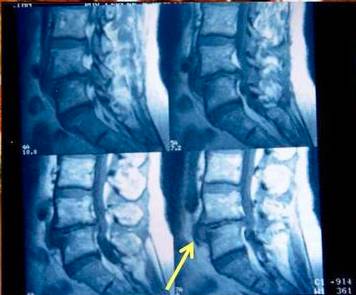

MRI:间盘前后方突出,椎间隙狭窄

椎间盘前方突出

经骨突出(schmorl结节)

MRI:巨大中央型突出

巨大中央型脱出